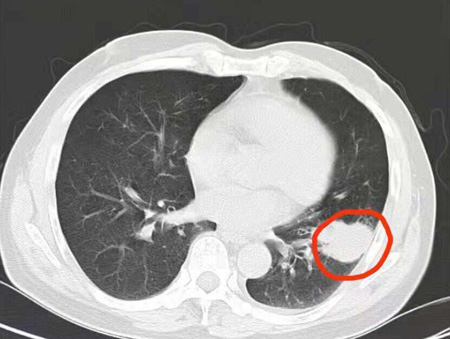

患者高先生因“反复咳嗽,体检发现肺占位1月余”入住玉溪市人民医院心胸外科。经检查,CT提示患者“左肺下叶团块状软组织密度影(约3.0×3.6cm),考虑周围型肺Ca可能性大”。心胸外科李轶峰医师在对高先生进行了详细的病情检查后,建议患者进行微创胸腔镜手术治疗。这种手术需要在侧胸壁开一个6cm小口即可完成,而且能整切除病灶、清扫淋巴结,不但切口美观、损伤较小,术后恢复较快、疼痛轻。

术前